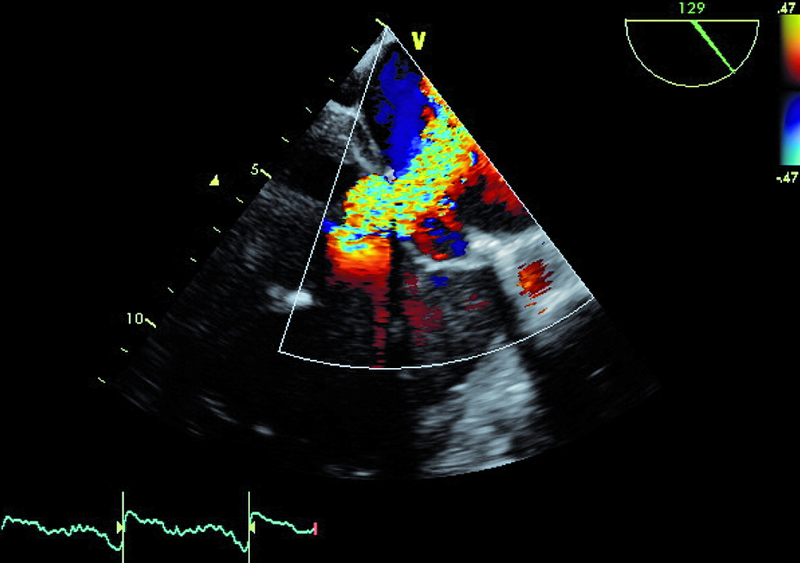

Mężczyzna, lat 68. Jakie patologie można rozpoznać na rycinach?

2. Duża niedomykalność zastawki mitralnej (ryc. 2, 5).